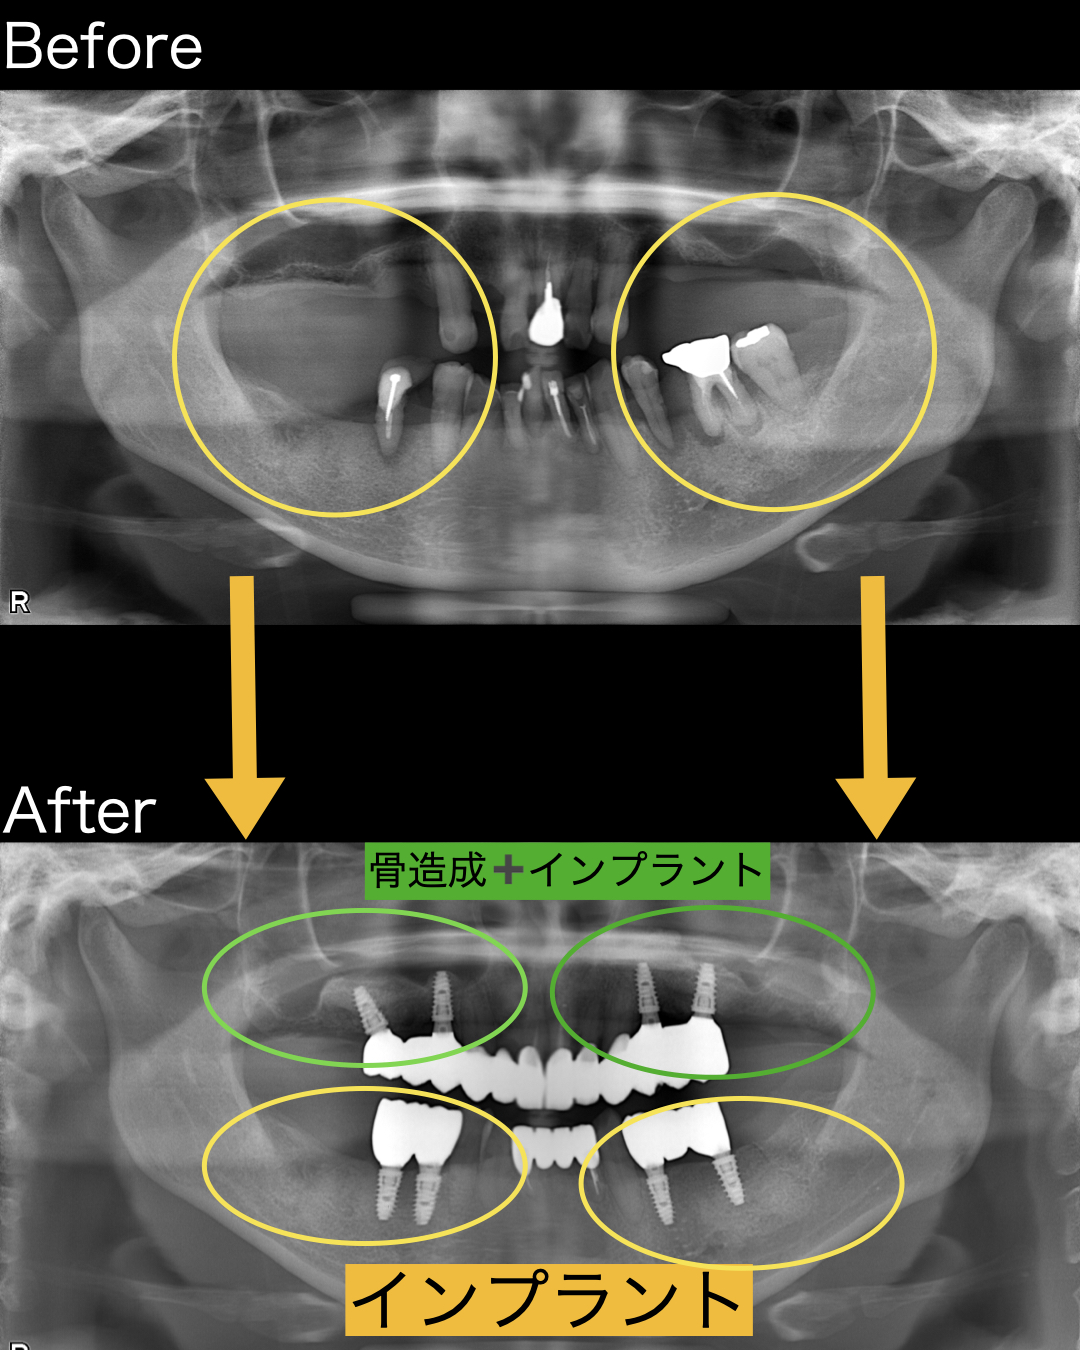

資料採取を行い分析の結果、かなり膿が大きかったのか炎症により骨は少なくなっていました。2〜3ミリほどしかなく骨造成が必要なことを説明し了承の上治療をスタートしました。

残念ながら下の前歯は歯周病により保存不可能な歯は数本抜歯させて頂きました。上の前歯は歯茎を整え根の治療を行えばまだまだ残せると判断し、根管治療を行いました。その間に左右の奥歯に大幅な骨造成(サイナスリフト)を行い、骨が硬化するまで半年ほどの治癒期間を設けました。その間に他の部位の治療と仮歯を入れました。

インプラント手術は下顎から行いました。上顎は骨がないので骨造成を行いましたが、下顎は骨が十分にあったため、他の治療と同時並行でインプラント埋入を行いました。

上顎の奥歯は骨造成サイナスリフトを行って6ヶ月待ったあとに、インプラント埋入を行いました。治癒経過もよく骨も硬くなっていたので、通常通りインプラント埋入を行えました。まずは右側を行い、その後に左側、2ヶ月ほどで生着がみられたので仮歯を入れ噛めるようにし、噛み合わせ、頬や舌を噛まないか、見た目などの審美的な面もすべてチェックを行いました。問題がないことを確認したあとに最終的なインプラントの上部構造であるセラミックをセットすることができました。